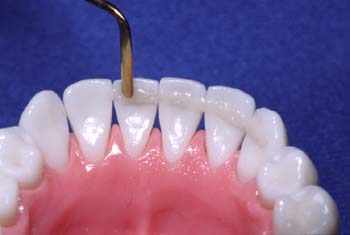

Prepare los dientes para la adhesión utilizando su procedimiento habitual. Aplique una capa delgada de pasta de resina al nivel de los contactos interproximales

Humedezca la fibra Ribbond con un adhesivo sin relleno (sellador). Adapte la fibra en el composite. Al igual que con los brackets, el retenedor fijo de Ribbond debe estar unido al diente lo más estrechamente posible.

Sujete con el dedo la fibra ya adaptada. Utilice un instrumento para colocar la fibra en los contactos interproximales lo más cerca posible de la superficie del diente. Continúe diente tras diente hasta colocar todo el retenedor.

La colocación de un retenedor Ribbond es diferente al de un alambre. Ribbond se adapta lo más cerca posible y muy profundamente en los contactos interproximales.